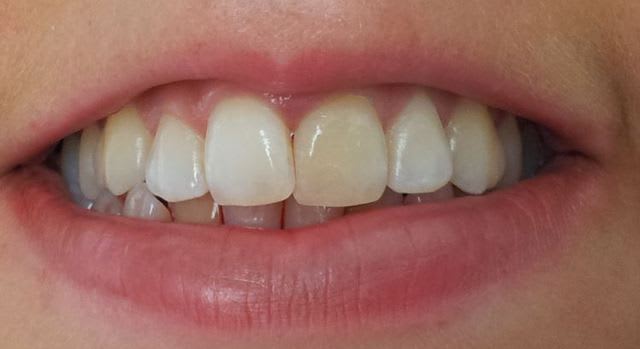

Bonjour, que me proposez vous pour cette jeune demoiselle de 21 ans....

Pas d'antécédent de choc, le canal a quasiment disparu radiologiquement, dent ne répondant pas aux tests de vitalité.

Dyschromie 21 sourire cupslo - Eugenol

il faudra aussi regarder la 42 qui a l'air sombre aussi

Et surtout l'occlusion: fonction canine inversée apparemment, version 22......et sûrement plein d'autres trucs ( mais là faut demander a Enlay, c'est lui qui sait😜).

Même si la radio n'est pas très nette, la photo est parlante. En l'absence de tout symptôme il serait suicidaire de tenter un traitement canalaire !

Reste la gêne esthétique ...